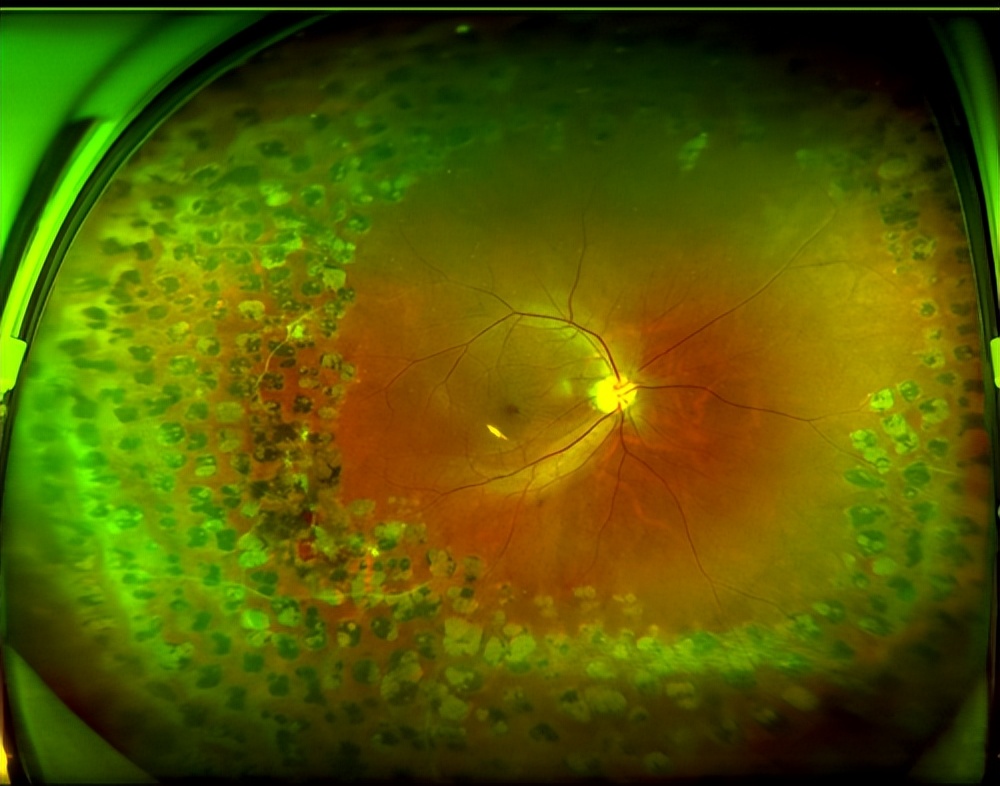

自20世纪90年代末在广州中山大学中山眼科中心攻读博士学位时起,赵教授便一直专注于各类黄斑疾病,尤其是黄斑裂孔的诊断与显微手术治疗。面对张先生左眼的黄斑裂孔,她立刻察觉到了情况的不同寻常——患者当时仅45岁,且无外伤史。经过散瞳后对视网膜周边部的详细检查,发现其双眼视网膜周边部均存在末梢血管白鞘和闭塞现象。随后进行的荧光眼底血管造影检查,进一步验证了赵教授的推断:张先生的左眼黄斑裂孔,属于一种较为罕见的、继发于视网膜静脉周围炎的类型。

接下来面临的就是治疗方案的选择——治疗的先后顺序,以及远期疗效怎样?相关的文献报道极为有限,治疗方案只能依据病史、眼部临床表现仔细分析后综合制定。最终,赵教授为张先生施行了27G微创玻璃体视网膜手术,成功修复了左眼300多微米的黄斑裂孔。术后视觉功能恢复显著,视力从术前的0.2提升至1.0。

“因双眼在外院做过多次视网膜激光光凝术,视网膜周边形成了多量点状激光瘢痕。这些瘢痕与正常视网膜粘连紧密,大大增加了手术的复杂性和风险。对主刀医生的技术要求高——需要更丰富的经验、更精湛的显微手术技术,以及应对复杂组织变化的能力。”